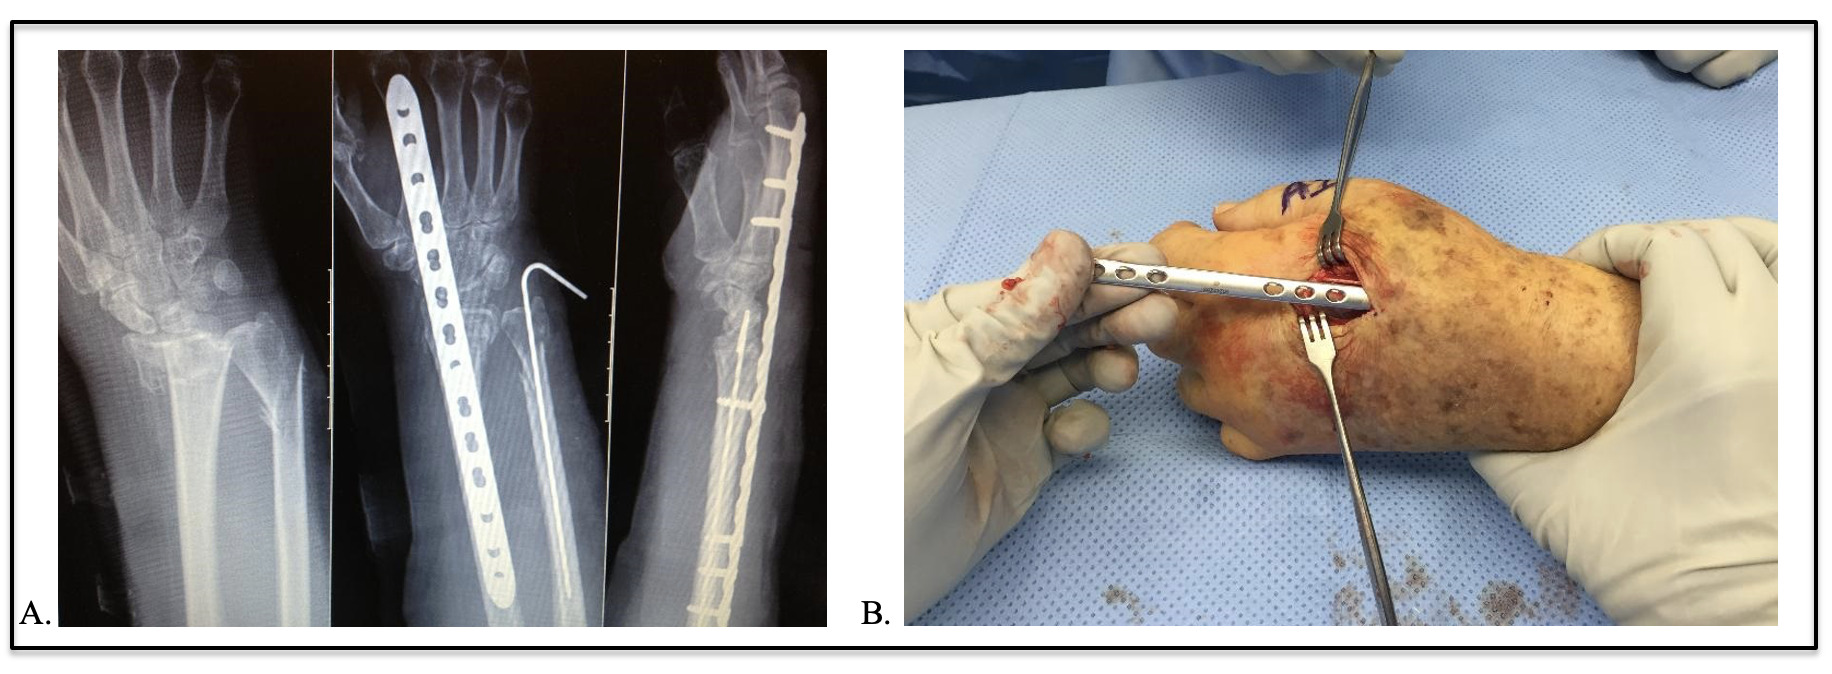

Distal radius fractures (DRFs) are among the most common fractures.1 While nonoperative treatment is common, surgical fixation is often indicated for patients who use their hands to ambulate, termed a functional quadruped, such as those who are walker-dependent or poly-traumatized, requiring crutches or other ambulatory assistive devices.2,3 Dorsal spanning bridge plate fixation has recently been popularized to manage fracture fixation in functional quadrupeds as it allows immediate weight-bearing across the injured wrist4,5 This technique initially utilized a dynamic compression plate; however, lower-profile anatomic locking plates have become more available [Figure 1].4

A 63-year-old, right-hand dominant female, previously an independent ambulator, presented following a fall from standing, incurring left hip and left distal radius fractures. After hip fracture repair, a dorsal spanning 2.4mm locking distal radius bridge plate (DePuy Synthes, West Chester, PA) was applied using the standard technique to allow for immediate weight-bearing with the injured wrist when using an ambulatory assistive device.